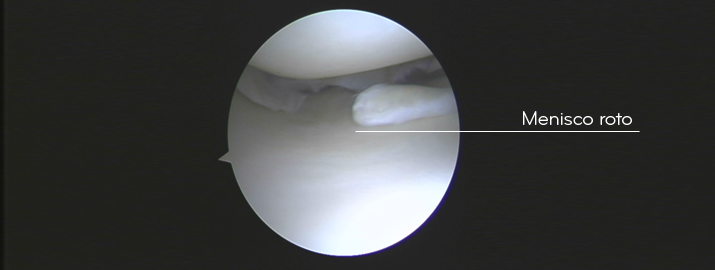

El menisco que más frecuentemente se afecta es el menisco interno, concretamente la parte posterior. Sin embargo, puede lesionarse cualquier parte, dependiendo del movimiento realizado. Debido a la forma especial de aporte sanguíneo del menisco, hay 2 tipos de rupturas: las localizadas en la zona central (donde no llega sangre y hay que resecar la lesión, ya que no cicatriza) y las más periféricas (donde sí llega aporte sanguíneo y es posible suturar y conservar).

Cuando se rompe ‘todo el menisco’ y hay que resecarlo, la presión entre fémur y tibia aumenta hasta un 300 %, provocando el desgaste del cartílago de la rodilla a medio plazo y la consiguiente artrosis precoz. Es por esto que, siempre que sea posible, hay que intentar conservar el menisco y suturarlo. Actualmente, puede realizarse la sutura del menisco mediante artroscopia sin problemas, permitiendo conservar el ‘amortiguador’ natural de la rodilla.

Sin duda alguna, siempre que se pueda, hay que REPARAR EL MENISCO (Save the meniscus!). Como hemos dicho, las lesiones en la periferia del menisco tienen capacidad de cicatrización por el aporte sanguíneo que les llega, así pues, hay que intentar coserlas SIEMPRE. En cambio, las lesiones que se producen en la parte central del menisco, no tienen capacidad de cicatrización y hay que acabar quitándolo. Si podemos conservar el menisco en su totalidad, evitaremos las secuelas a largo plazo debido a la falta de “amortiguación” que produce. Pero, repito, todo esto depende del tipo de lesión de menisco que se haya producido, no de la capacidad técnica que tengamos para repararlo o no.